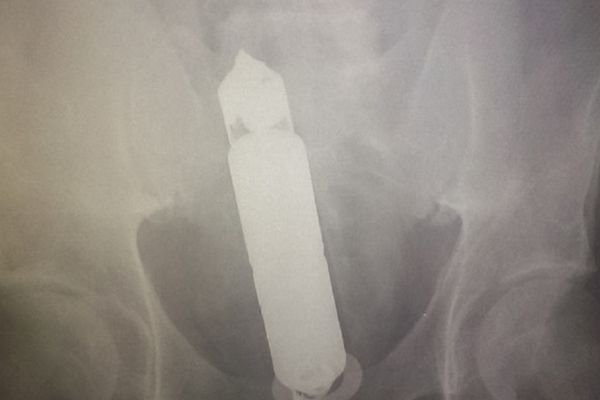

Nevaljali dekica (68): Na rendgenu mu našli seks igračku u stomaku!